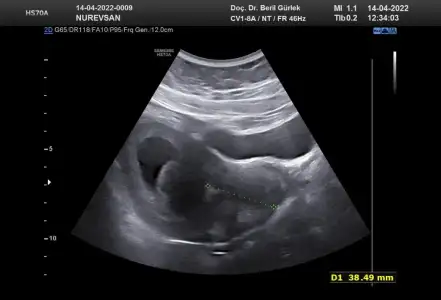

Ay ne güzel başlık banada tahmın edebılır mısın😊🤗 burda 8 haftalık karından bakıldı sımdı 10 haftalıgım 2 hafta sonra gidicem doktora bır tahmınde bulınabılır mısın

Eklentiler

• IMG-20220414-WA0006.webp

IMG-20220414-WA0006.webp

23,5 KB · Görüntüleme: 92

Burada 8 haftalık karından canım